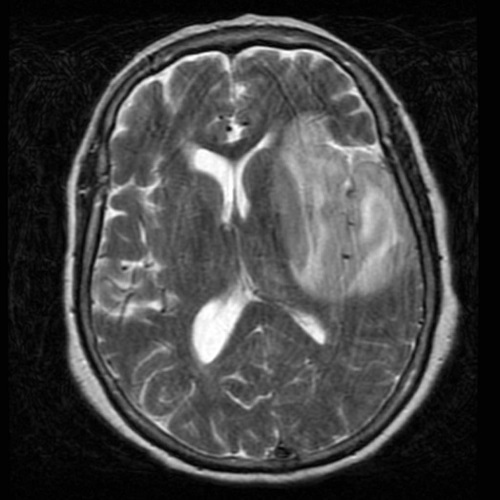

MRI of a patient with HSV encephalitis. There is hyperintensity of the affected white matter and cortex in the medial temporal lobes and insular cortex.